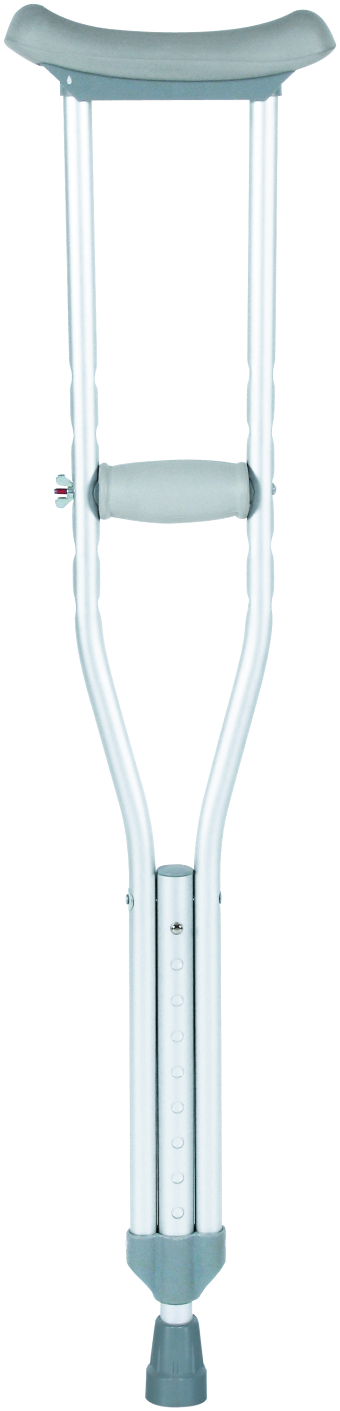

- Crutches

Crutches are an important medical rehabilitation AIDS, branch cane, elbow crutches, axillary crutches, multi-foot crutches, crutches play an important role in walking, not only to provide support and balance, but also to help improve gait and reduce energy consumption